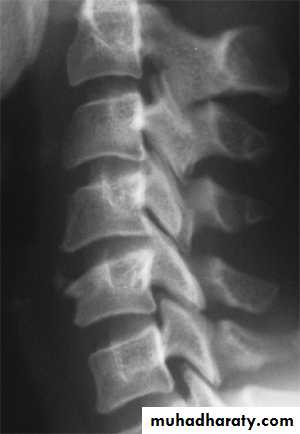

Flexion and flexion-rotation injuries

frcature spine and peripheral nerve

are common:

flexion alone tends to a wedge compression fracture .

whereas combined flexion and rotation cause subluxation ,

dislocation or fracture-disIocation.

DIAGNOSISX RAY

Anterio posterior X ray radiograph.lateral radiographs with the head in flexion and extension may revealinstability that is not shown in the routine lateral film.

Wedge compression fracture of a vertebral body.

WEDGE COMPRESSION FRACTURE